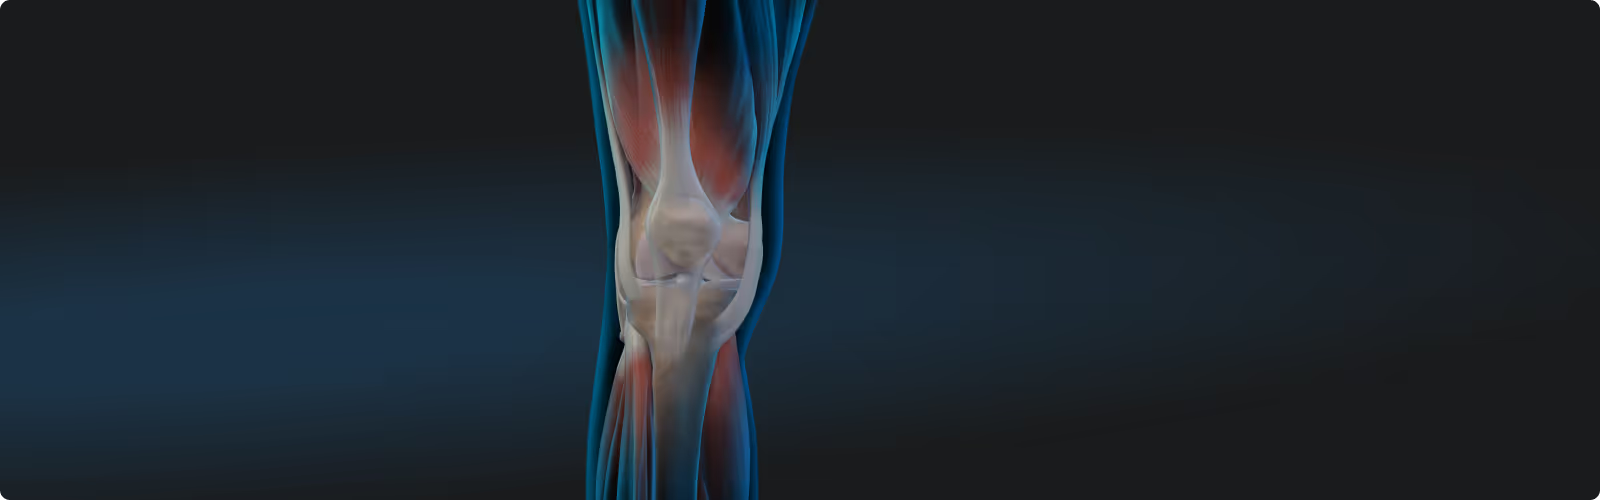

Select your application area and learn how to support your patients' recovery at the cellular level: